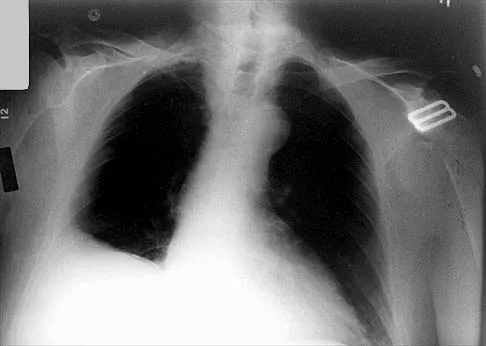

Which of the following findings is seen in the chest radiograph shown in Figure 13?

Explanation

Orthopaedic surgeons are often responsible for interpreting radiographs of general examinations such as the chest radiograph shown. For accurate interpretation, it is important to systematically review all of the information available on the radiograph. Using this approach, the fracture of the left proximal humerus is readily recognized. Linear air soft-tissue density at the lung periphery would suggest a pneumothorax, but this finding is not shown on the radiograph. The upper thoracic spine is well aligned. The sternoclavicular and distal clavicles are normal.